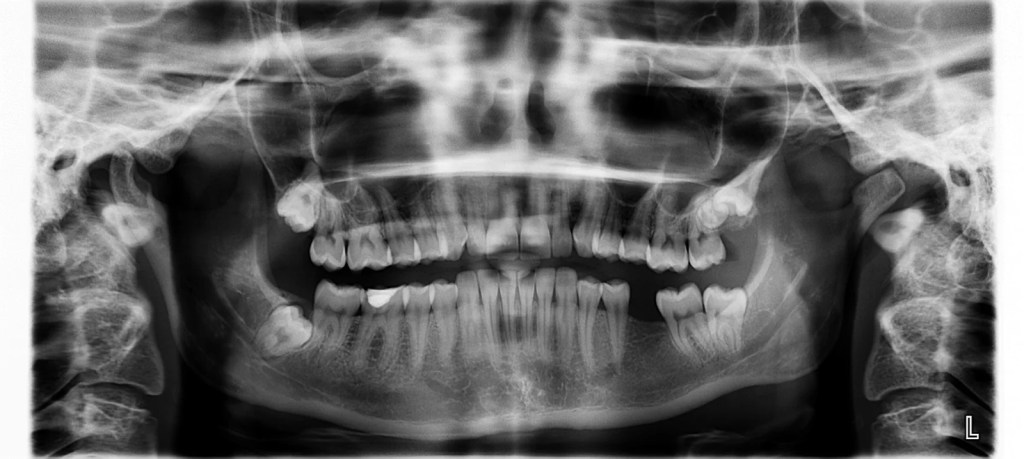

Filme Radiográfico Panorâmico

O filme panorâmico proporciona uma visão abrangente das arcadas dentárias, ossos maxilares e estruturas adjacentes.

É amplamente utilizado para avaliação inicial de pacientes, planejamento ortodôntico, identificação de terceiros molares inclusos e acompanhamento de fraturas mandibulares.